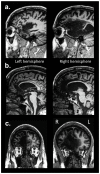

It has been proposed that self-awareness (SA), a multifaceted phenomenon central to human consciousness, depends critically on specific brain regions, namely the insular cortex, the anterior cingulate cortex (ACC), and the medial prefrontal cortex (mPFC). Such a proposal predicts that damage to these regions should disrupt or even abolish SA. We tested this prediction in a rare neurological patient with extensive bilateral brain damage encompassing the insula, ACC, mPFC, and the medial temporal lobes. In spite of severe amnesia, which partially affected his "autobiographical self", the patient's SA remained fundamentally intact. His Core SA, including basic self-recognition and sense of self-agency, was preserved. His Extended SA and Introspective SA were also largely intact, as he has a stable self-concept and intact higher-order metacognitive abilities. The results suggest that the insular cortex, ACC and mPFC are not required for most aspects of SA. Our findings are compatible with the hypothesis that SA is likely to emerge from more distributed interactions among brain networks including those in the brainstem, thalamus, and posteromedial cortices.